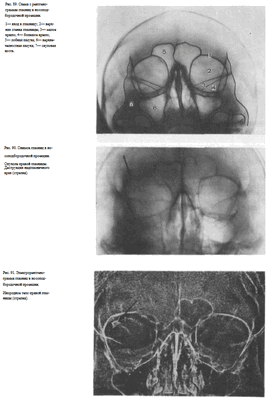

УКЛАДКИ СНИМОК ГЛАЗНИЦЫ В НОСОПОДБОРОДОЧНОЙ ПРОЕКЦИИ

Назначение снимка. Изучение состояния костей, образующих вход в глазницу, костной структуры верхней и наружной ее стенок.

Укладка больного для выполнения снимка сходна с укладкой для выполнения обзорного снимка в этой же проекции. В данном случае используюткассету размером 13X18 см, располагая ее в кассетодержателе в поперечном положении. Больной прилежит к столу подбородком и кончиком носа,переносье соответствует центру кассеты. Центральный пучок излучениянаправляют на центр кассеты. Фокусное расстояние—100 см.

В этой же укладке может быть выполнен снимок одной (правой или левой) глазницы. В таких случаях центр снимаемой глазницы соответствует центру кассеты, и на него отвесно направляют пучок излучения, используя тубус или диафрагмирование пучка излучения с помощью щелевой диафрагмы. Фокусное расстояние—100 см (рис. 88).

Информативность снимка. На снимке хорошо видны вход в глазницу, структура ее стенок, иногда малое и большое крыло клиновидной кости (рис. 89). На снимке в этой проекции могут быть выявлены деструктивные изменения стенок глазницы и инородные тела в ее полости (рис. 90, 91). Для выявления изменений в области верхней стенки глазницы (например, при

На прицельном снимке каждой из глазниц в этой же проекции, как правило, небольшие изменения структуры стенок, а также мелкие инородные тела глаза видны лучше. Такие снимки широко используют в офтальмологической практике (рис. 92).

Критерии правильности технических условий съемки и правильности укладки основываются на четкости выявления костной структуры и симметричности изображения глазниц.

Наиболее частые ошибки при выполнении снимка сводятся к асимметрии положения головы.